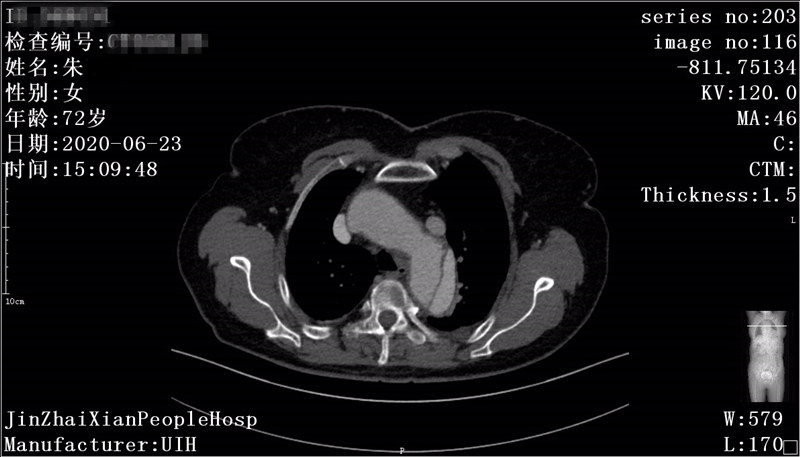

患者汪某,女,62岁,家住我县天堂寨镇,患者源于2年前无明显诱因下出现胸背部疼痛,外院检查后确诊"主动脉夹层",曾行"主动脉覆膜支架腔内隔绝术"。术后反复出现胸背部疼痛不适,伴有胸闷、咳嗽症状,休息后可好转。因上述症状加重就诊我院呼吸内科,门诊查主动脉全程增强CTA见主动脉弓边缘见一直径约11mm破口影,造影剂经破口流入主动脉周围血肿内。CTA提示:主动脉夹层,患者为求进一步诊治遂至介入科就诊,拟"主动脉夹层"收住入院。入院后我科积极完善相关术前准备及检查,于 7月5日在DSA下行“主动脉、双侧颈总动脉、左锁骨下动脉造影+分支型覆膜支架腔内隔绝术+左锁骨下动脉开窗覆膜支架植入术+胸主动脉覆膜支架植入术”。术后病情平稳,现患者胸闷症状消失、咳嗽明显好转。

术前CTA见造影剂经破口处外溢